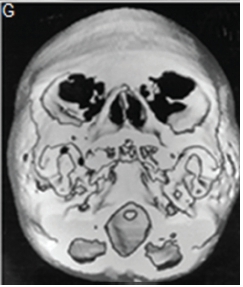

A diagnosis of Apert syndrome was made. Apert syndrome is a rare developmental condition characterized by premature cranial synostosis and resultant growth disturbances. Signs of Apert syndrome include a peaked and vertically elongated head, widespread bulging eyes, and a protuberant frontal region with an anteroposterior ridge overhanging the frontal eminence (Figure A). The palate is high, arched and occasionally cleft (Figure B). There is hypoplasia of the maxilla with relative prognatism of the mandible. Dental malocclusions with crowding and delayed dental eruption in the maxilla are common (Figure C). The facial angle is exaggerated; the nose is small and has been compared to a parrot's beak in appearance. Hypertelorism, exophthalmos and divergent strabismus are often present; sometimes with blindness. Spina bifida has been recorded in some patients. Syndactyly of the hands and feet varies greatly. Hand films in Apert syndrome showing syndactyly with fusion of three fingers in both hands and webbing (Figure D). Syndactyly of the feet in the same patient is also discernible (Figure E) Note the tall (turricephalic) skull, open metopic suture, and faint beaten-silver appearance of the calvarium. Skull base and roof of the calvarium are flattened, with a noticeable beaten-silver appearance (Figure F). The 3-D CT reconstruction of the same patient showing hypoplastic maxilla with posterior cleft (Figure G) The patient may be retarded or of normal intelligence. Apert syndrome may be associated with advanced paternal age. The cardinal radiologic features of Apert syndrome are: Brachycephalic (reduced anteroposterior dimension of the skull with increased skull width). Turricephaly (occurrence of a skull with high vertical index), beaten silver appearance of the calvarium, absence of demonstrable cranial sutures in coronal dimension in young patients, hypoplastic maxilla and syndactyly of the hands and feet. Differential Diagnosis: Crouzon's disease, Pfeifer syndrome, Carpenter syndrome and Summit syndrome.